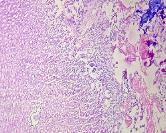

All the animals were observed daily for clinical signs of toxicity and morbidity. Individual animal body weights were recorded at receipt (on day 1) and weekly thereafter and at the time of sacrifice (fasting body weights). Histological examinations of various organs (brain, kidney, liver, small intestine and stomach) were carried out after 28 d using haematoxylin and eosin as staining agents. The organs were preserved in 10 % formalin solution.

On administration of TPSY, the animals in all groups were found to survive at the end of 28 d of study. The histological results are shown in table 4. Liver tissue showed minimal degeneration of hepatocytes compared to control at the highest dose of 350 mg which was however reported to be non-toxic.

Mild tubular degeneration was observed in kidneys Stomach tissue displayed moderate changes compared to control, with minimal degeneration of mucosal cellsat highest dose of 350 mg. Large intestine showed marked submucosal edema but the mucosal tissue appeared to be normal at the highest dose of 350 mg. No abnormality was observed in brain tissues at a low and medium dose. Mild submucosal edema was observed at 350 mg/kg. These results point to the negligible toxicity associated with the thiolated polymer and hence it can be considered to be safe for use as a pharmaceutical excipient.

Table 4: Histological results of repeated dose toxicity studies of TPSY (n=5)

| Organs | Normal saline | TPSY dose strength | ||

| Control | 70 mg/kg | 175 mg/kg | 350 mg/kg | |

| Liver | Normal architecture of liver, nothing abnormal detected. | Nothing abnormal detected. | Minimal degeneration of hepatocytes. | Minimal degeneration of hepatocyte and infiltration of inflammatory cells. |

| Kidney | Normal architecture of kidney, nothing abnormal detected. | Minimal tubular degeneration. | Mild tubular degeneration and congestion of blood vessels. | Mild tubular degeneration. |

| Stomach | Normal architecture of Stomach, Nothing abnormal detected. | Minimal degeneration of mucosal lining cells. | Mucosal cells were enlarged and were darkly stained. | Minimal degeneration of mucosal cells, accumulation of dark staining material in the gland. |

| Brain | Normal architecture of the brain, Nothing abnormal detected. | Nothing abnormal detected. | Nothing abnormal detected. | Minimal neuronal degeneration. |

| Large intestine | Papillary projections with goblet cells. | Mucosal lining no infiltration of inflammatory cells. | Minimal infiltration of inflammatory cells and congestion. | Marked submucosal edema, mucosal tissue appears normal. |

Fig. 8: Histology of various tissues at highest dose strength of 350 mg/kg body weight